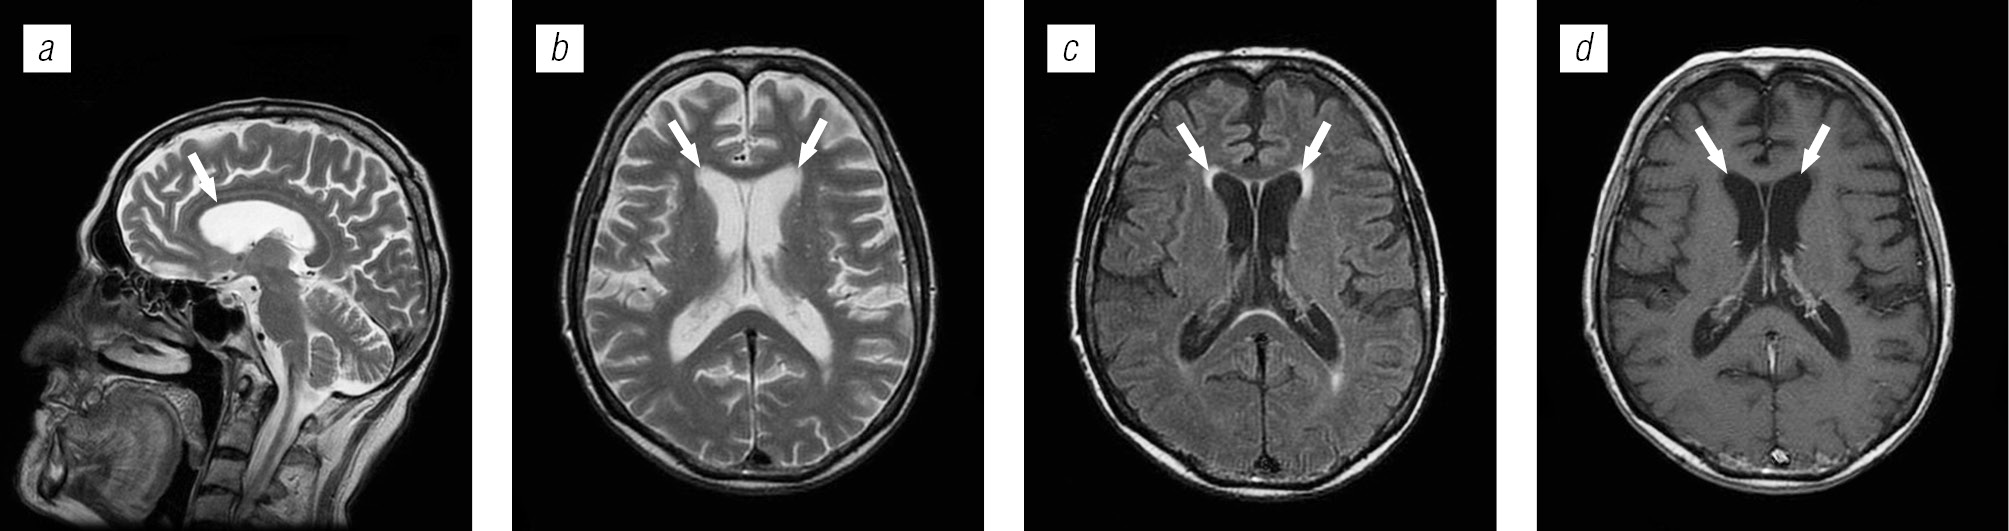

Структура поражения головного мозга у ВИЧ-инфицированных больных имела различную природу: в 54,4 % случаев обнаружены признаки оппортунистических и вторичных заболеваний, в 24,9 % — признаки ВИЧ-энцефалопатии, в 13,2 % — признаки неспецифических изменений мелких сосудов головного мозга, указывающие на преждевременное старение или аномалию развития; в 7,56 % признаки вовлечения головного мозга в патологический процесс не выявлены.

Структура оппортунистических и вторичных заболеваний была представлена токсоплазмозом головного мозга (18,3 %), герпесвирусными поражениями (12,2 %), прогрессирующей мультифокальной лейкоэнцефалопатией (10,24 %), нейроинфекцией неуточненной этиологии (12,2 %), криптококкозом (4,39 %), туберкулезом (2,44 %), лимфомой головного мозга (2,44 %), МАК-инфекцией (0,24 %).